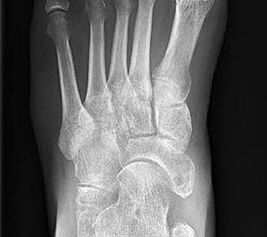

Stehende konventionelle Röntgenbilder eines Fußes mit Planovalgus Deformität Stadium II b dorsoplantar (dp) und seitlich. Auf der dp-Aufnahme zeigt sich die talo-calcaneare Divergenz, der gegenüber dem Kalkaneus nach anterior gleitende Talus und d

Abbildung 5

Stehende Aufnahmen des Fußes dorsoplantar (dp) und seitlich sowie des OSG anteroposterior (ap) sind die Grundlage der konventionellen Röntgendiagnostik (Abb. 5). Ergänzend werden gelegentlich die Rückfuβ-Alignement Aufnahme nach Saltzman 19 und Vergleichsaufnahmen der Gegenseite durchgeführt.

Der Talo-Metatarsale I Winkel bzw. die laterale talonaviculare Subluxation auf der stehenden dorsoplantaren Aufnahme des Fuβes dokumentieren das Ausmaβ des Vorfuβ abductus (Abb. 6 a,b). Ein dp Talo-Metatarsale I Winkel von > 10° (nach medial konvex) ist als pathologisch anzusehen. Mit der Bestimmung der talocalcanearen Divergenz (Abb. 6 c) erhält man ein Eindruck über das Ausmaβ des Rückfuβ valgus; eine leichte Divergenz bis ca. 12° gilt als physiologisch 20.